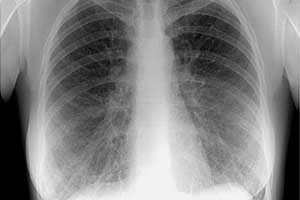

Снимок здоровых лёгких

При оценке результатов цифровой флюорографии врачи рассматривают следующие позиции при помощи рентгеновского облучения:

- мягкие ткани;

- целостность костных элементов;

- расположение трахеи;

- наличие кальцинатов;

- контуры сердца;

- лёгочные поля.

Исследование проводится в передне-задней проекции. Снимки информативны и дают возможность оценить или выявить наличие патологии в лёгких.